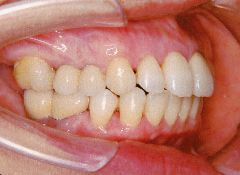

治療例1 (インプラント補綴+矯正)